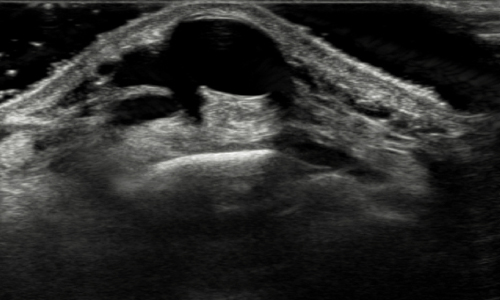

결절종

수부에 발생하는 가장 흔한 종양으로 손목의 관절을 둘러싸고 있는 얇은 성유성 피막 안에 투명하고 끈적이는 액체를 함유하고 있는 물혹성 종양입니다.

결절종 초음파 영상 사진